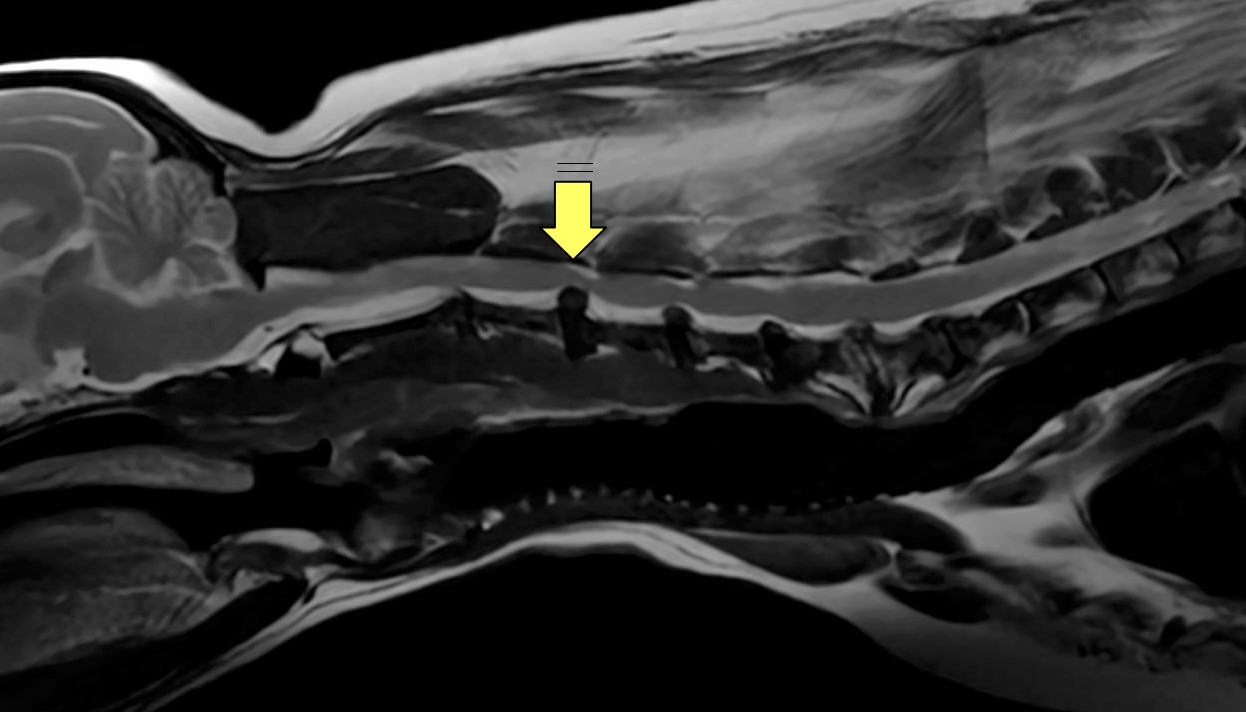

立てなくなってしまったとの主訴で来院された患者さんで、MRIの結果「頸椎3-4椎間板ヘルニア」と診断されました。

MRI画像:矢印の部分で椎間板の逸脱(ヘルニア)が観察されます